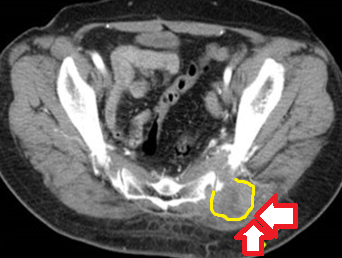

Αξονική τομογραφία κοιλίας. Φεβρουάριος 2017. Εμφανίζεται η υποτροπή του οπισθοπεριτοναϊκού αγγειοσαρκώματος (κόκκινα βέλη)